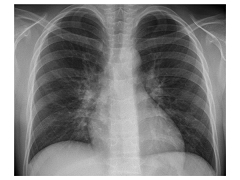

Physical examination. On the day of admission, laboratory test results showed an elevated C-reactive protein (CRP) level of 18.5 mg/dL (reference range, 0.08-3.1 mg/L), a white blood cell count of 11,000/μL (reference range, 45000-11,000/μL), a hemoglobin level of 12.1 g/dL (reference range, 14.0-17.5 g/dL), a hematocrit level of 36.1% (reference range, 41%-50%), and a platelet count of 538 × 103/μL (reference range, 150-350 × 103/μL). Urinalysis results showed a trace level of protein. Results of a comprehensive metabolic panel were within normal limits, and chest radiographs showed a cavitary lesion in the right upper lobe.

Due to the characteristic cavitary lesion on chest radiographs, suspicion for Staphylococcus aureus pneumonia was high; hence, treatment with an intravenous (IV) vancomycin and IV cephalosporin was initiated. Several days of antimicrobial therapy resulted in no clinical improvement. A computed tomography (CT) scan of the thorax showed a large cavitary air-space opacity in the right lung and perihilar region, areas of necrosis and cavitation, and dense consolidation in right lower lung.

A chest radiograph performed 6 weeks after initiation of treatment showed complete resolution of the pulmonary cavitary lesion.

Figure 1. A round cavitary lesion was visible in the right upper lobe.

Figure 4. A chest radiograph 6 weeks after initiation of treatment showed resolution of the right upper lobe cavitary lesion.